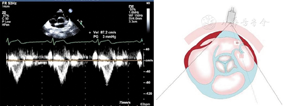

图5

胸骨旁主动脉瓣短轴切面,显示收缩期肺动脉峰值速度测量方法。在肺动脉瓣瓣上远心端1 cm处管腔中央获取

图6

胸骨旁右心室流出道切面,显示右心室流出道血流峰值速度测量方法。在肺动脉瓣瓣下2 cm处测量右心室流出道血流速度频谱